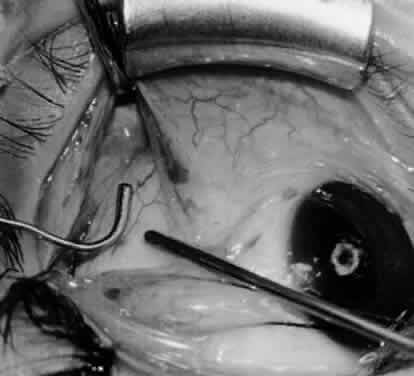

Fig. 24. The eyelid speculum is removed and a Desmarres lid retractor is placed inferiorly. The inferior oblique muscle is drawn superiorly and nasally. The fusiform expansion of the inferior oblique muscle is evident on the posterior border, where the nerve to the inferior oblique muscle and artery and vein enter the inferior oblique muscle. The Stevens muscle hook is used to hook the neurovascular bundle.

Fig. 25. The hook is advanced further for identification of the neurovascular bundle on the inferior oblique muscle.

Fig. 26. Cautery is applied to sever the neurovascular bundle, and a sponge is used to protect the sclera and lids from cautery.

Fig. 27. As the neurovascular bundle is severed completely, the inferior oblique muscle will be released of the normal tension provided by the neurovascular bundle on the posterior border of the inferior oblique muscle.